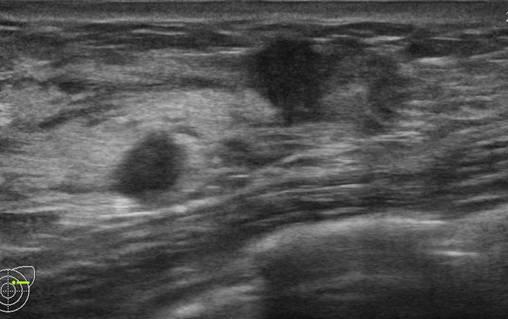

Ung thư vú

» Thông tin: Nữ giới – 25 tuổi.

» Lâm sàng: Khối tuyến vú.